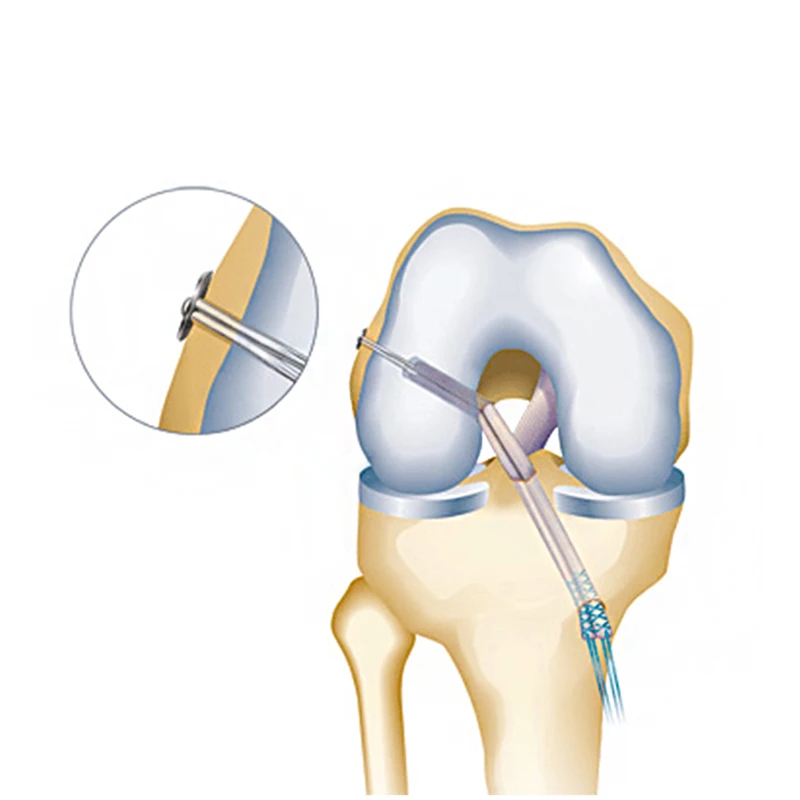

Пластика ПКС (артроскопия)